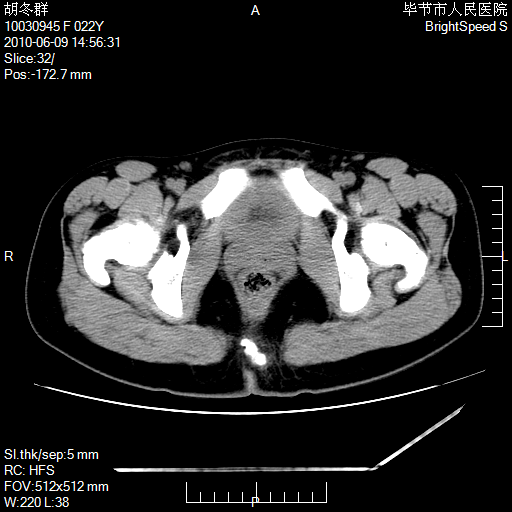

患者23岁,发现腹部包块3月。

盆腔内囊性占位;穿刺或者直接手术拿掉即可,不必紧张。

盆腔内囊性占位性病变;考虑左侧卵巢囊腺瘤。

有分隔、壁薄,支持考虑左侧卵巢囊腺瘤。

左侧卵巢浆液性囊腺瘤。

有分隔、壁薄,支持考虑左侧卵巢囊腺瘤。排尿后,膀胱缩小,由于重力作用,肿块下移就到了膀胱位置,很好理解。